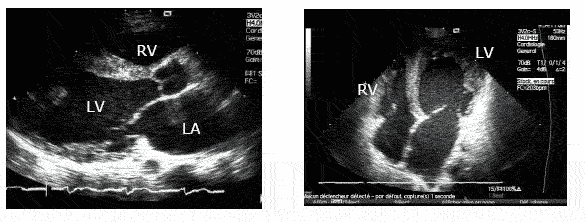

Measurement Of Left Ventricular Wall Thickness Eehocardiography

MEASUREMENTS BY ECHOCARDIOGRAPHY utilized to measure left ventricular wall thickness and mass and changes in the wall throughout the cardiac cycle, and these ... Read Here